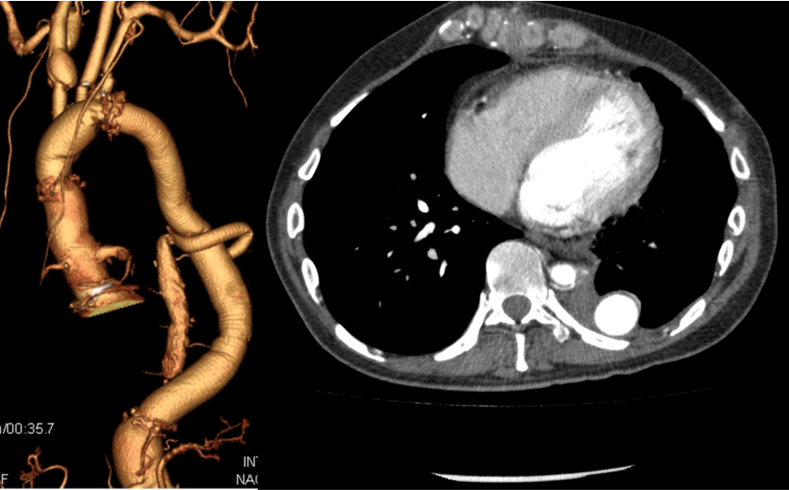

大動脈瘤(血管のこぶ)は「大動脈の一部の壁が、全周性または局所性に拡大または突出した状態」と定義され、その直径が正常径の1.5倍を超えて拡大した場合を指します。胸腹部大動脈瘤は、胸部と腹部を隔てる横隔膜にまたがる大動脈瘤のことであり、高血圧や大動脈解離などによる炎症が原因で発生します。

本邦のガイドラインでは、60mmを超えるものや半年で5mm以上拡大するものは特に破裂の危険性が高いといわれています。また60mmに満たなくても症状(痛み)のあるものは危険性が高いです。治療は開胸開腹下人工血管置換術、ステントグラフト内挿術が挙げられます。最近ステントグラフトによる治療が増えてきておりますが、人工血管置換術と比べて対麻痺を下げる結果には至っておりません。